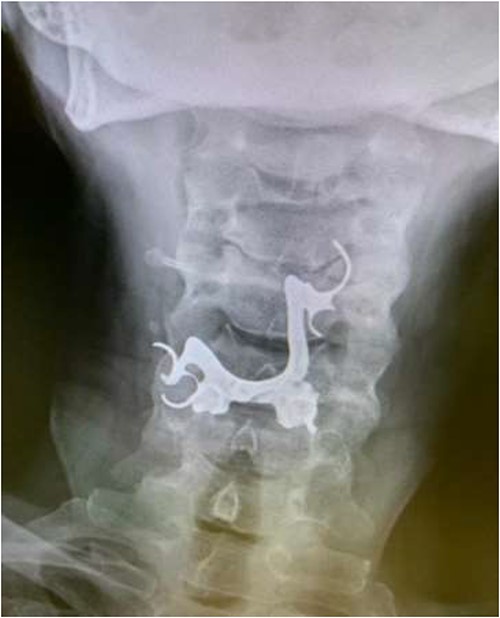

The final case is of a 75-year-old female who presented to hospital after inhalation of her dentures (Figs 6 and 7). After discussion with the anaesthetic team, apnoeic oxygenation was once again utilized in order to remove the foreign body without risk of dislodgement and to decrease the risk of a potential surgical airway (Fig. 8).

Anterior-posterior neck X-ray showing a radio-opaque object, in keeping with metal dentures.